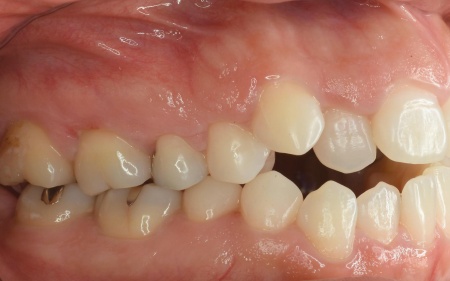

「奥歯で噛むと上下前歯が触れ合わないので、噛み合わせを治したい。また、歯並びがデコボコしているのも気になる」とご相談いただきました。

拝見したところ、奥歯で噛んだ際に上下の前歯が触れ合わず、隙間ができている状態でした。

これは開咬(かいこう)と呼ばれ、前歯で食べ物を噛み切るのが難しい噛み合わせです。

加えて全体的に歯が重なり合ってデコボコに生えており、歯磨きがしにくく、審美性にも悪影響がでています。

さらに舌で前歯を押す癖もあり、これは開咬の原因だけでなく、矯正治療後に歯並びが戻る原因にもなります。